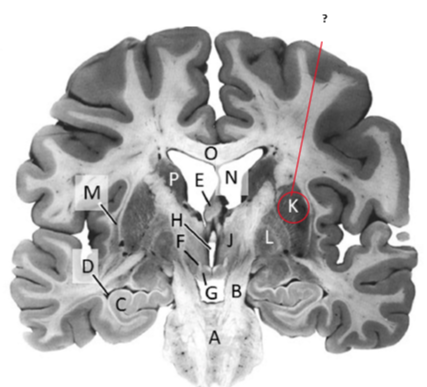

Name and state its function.

Lateral ventricles.

Name this, state its function and consequence of lesion in this area.

Fornix.

Transmits Theta waves aswell.

Lesion: anterograde amnesia.